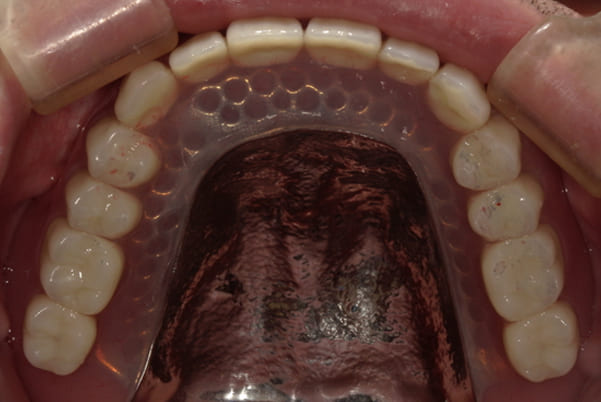

治療前後の口元の比較

こちらは、口を少し開いた時の治療前と治療後の

口元です。

正面から見た時にクラスプが目立たないように、

歯ぐきになじむ素材にて入れ歯を製作し、痛くなく自然に馴染み快適に生活を送れるようになりました。